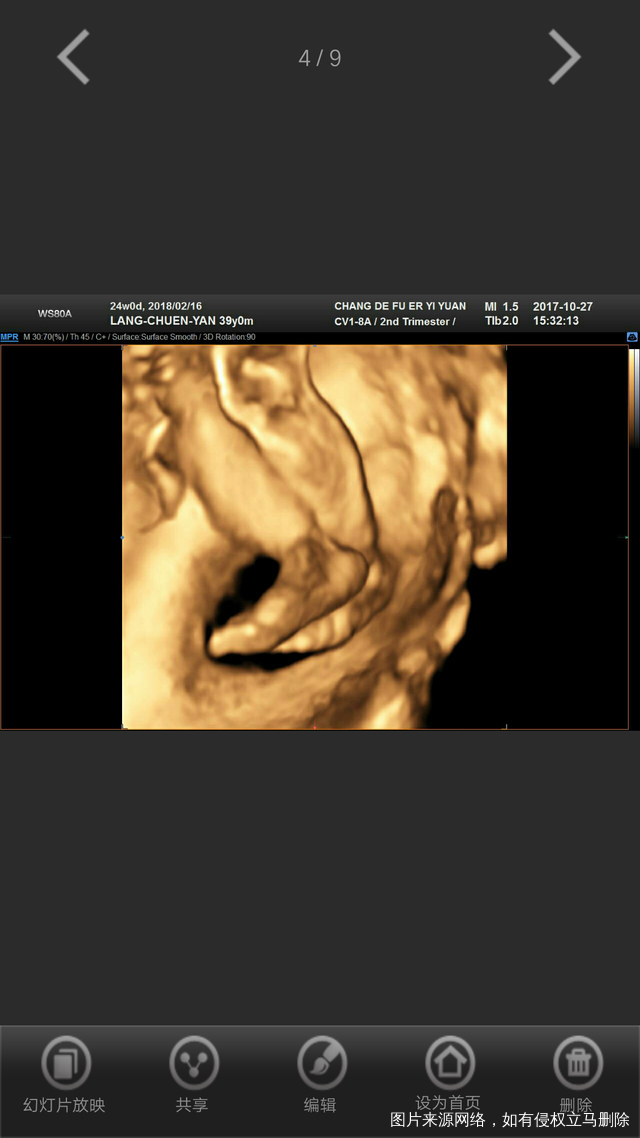

今天36周加两天了,算算日子也挺快的(⊙o⊙)哦[大笑]累快乐着